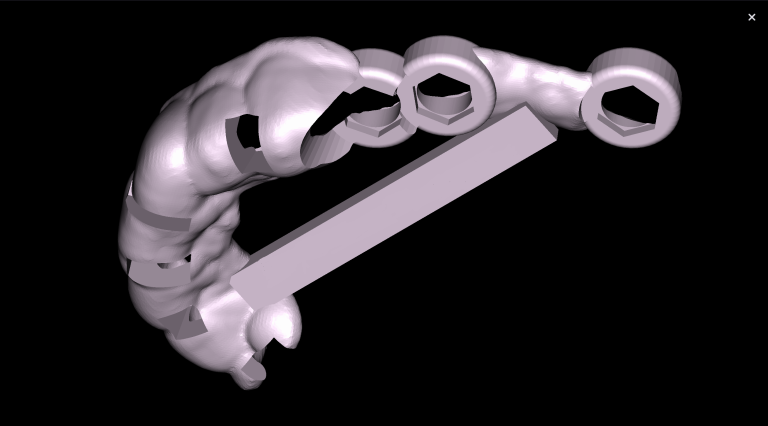

We start by loading the intraoral scan data into the Diagnocat STL module and getting a 3D model for choosing the optimal spatial position of the implant and planning the virtual design of the template for guided implant surgery